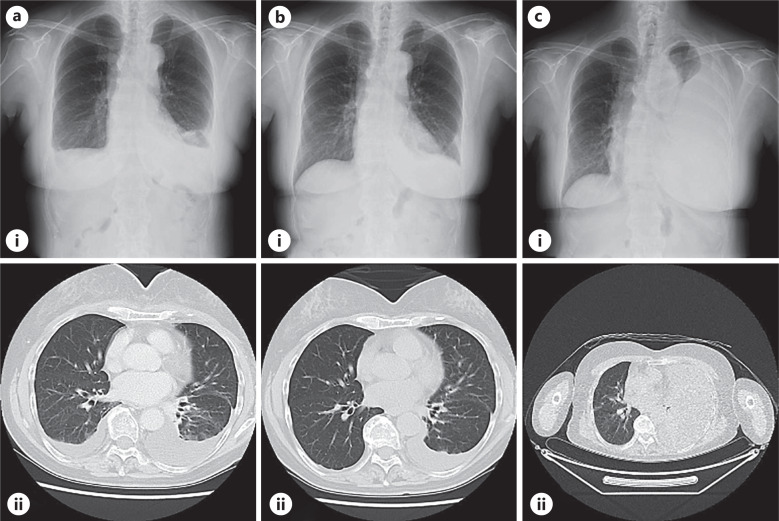

Case presentation: A 66-year-old woman presented with bilateral chylothorax that was initially suspected to be a lymphoma. After a transient resolution, the pleural effusion returned on the left side, with a shift from chylous to non-chylous fluid and an increase in carcinoembryonic antigen levels. Despite endoscopic findings resembling early stage gastric cancer, cytology confirmed SRCC. Despite treatment with capecitabine plus oxaliplatin and nivolumab, the disease progressed, resulting in bilateral effusion recurrence and death within 4 months. Genetic analysis revealed CLDN18.2 positivity.

Conclusion: This case is unique because it demonstrates a rare progression from bilateral to unilateral pleural effusion, accompanied by a transition in pleural fluid characteristics, which has not been previously reported. The observations suggest dynamic changes in lymphatic obstruction and tumor infiltration. Early molecular profiling, which includes CLDN18.2 testing, may provide new opportunities for targeted therapy in aggressive gastric cancer cases.